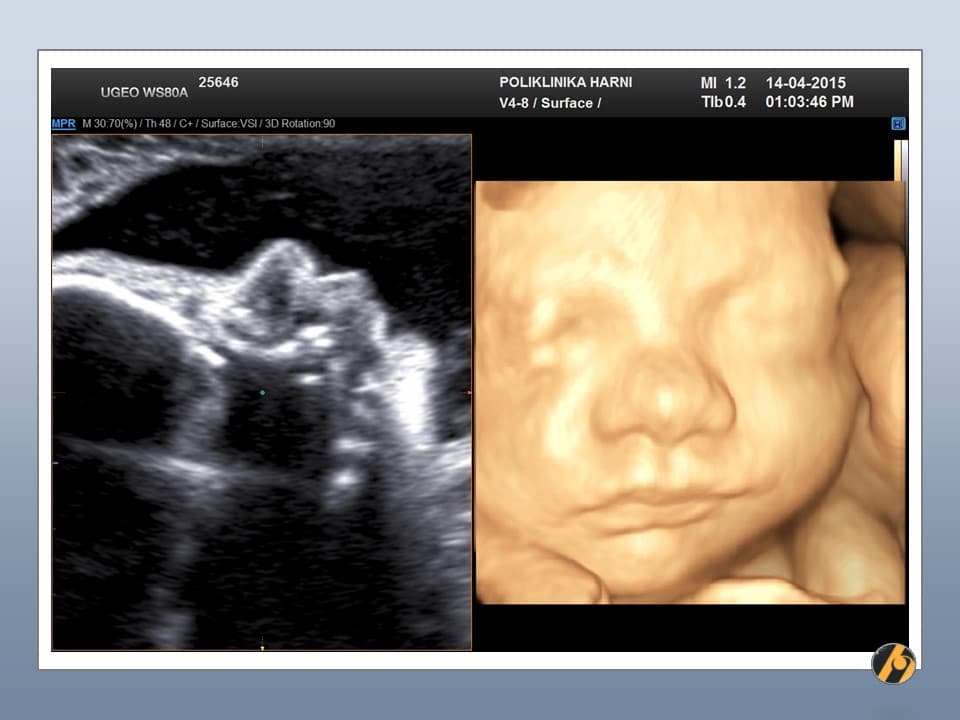

Vaša beba dugačka je oko 44 cm, a teška 2,300 – 2,550 g.

beba